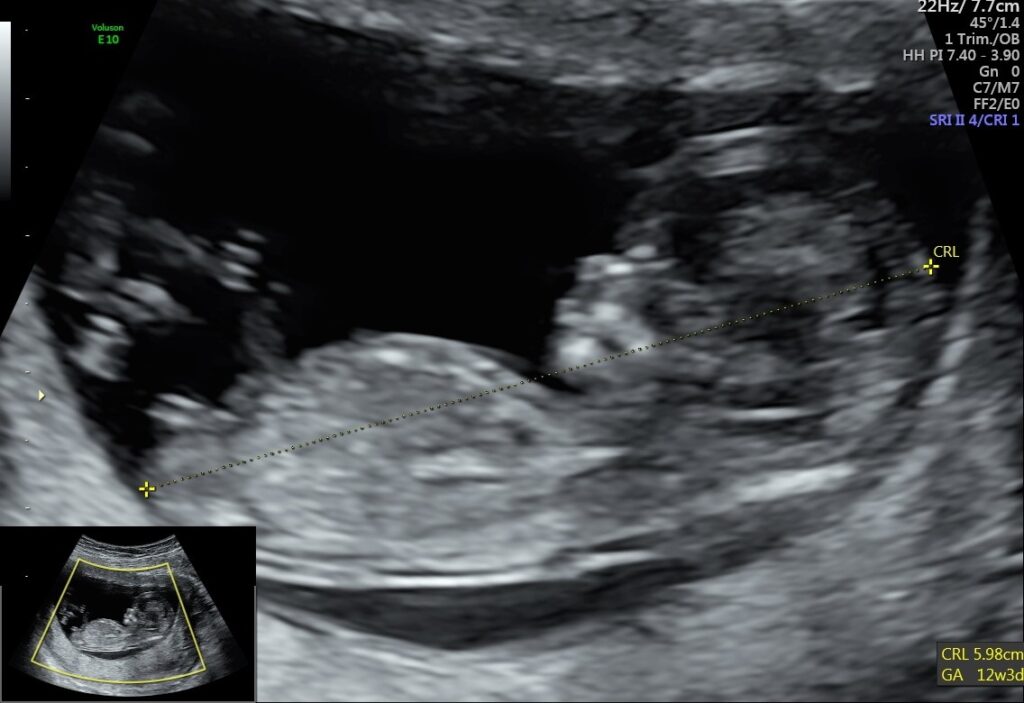

• USG I trymestru, tzw. genetyczne (11-14 tyg.),

W Aurea MED oferujemy pełną gamę nieiwazyjnych badań prenatalnych. Wykonujemy USG 1, 2 i 3-go trymestru, które przeprowadzają lekarze mający wymagane certyfikaty i ogromne doświadczenie w tym zakresie. Wiemy, że samo badanie USG – nawet najlepiej wykonane – pozwoli wykryć 60-70% wad chromosomowych dlatego zawsze rekomendujemy wykonanie badań biochemicznych (tzw. test podwójny i potrójny).